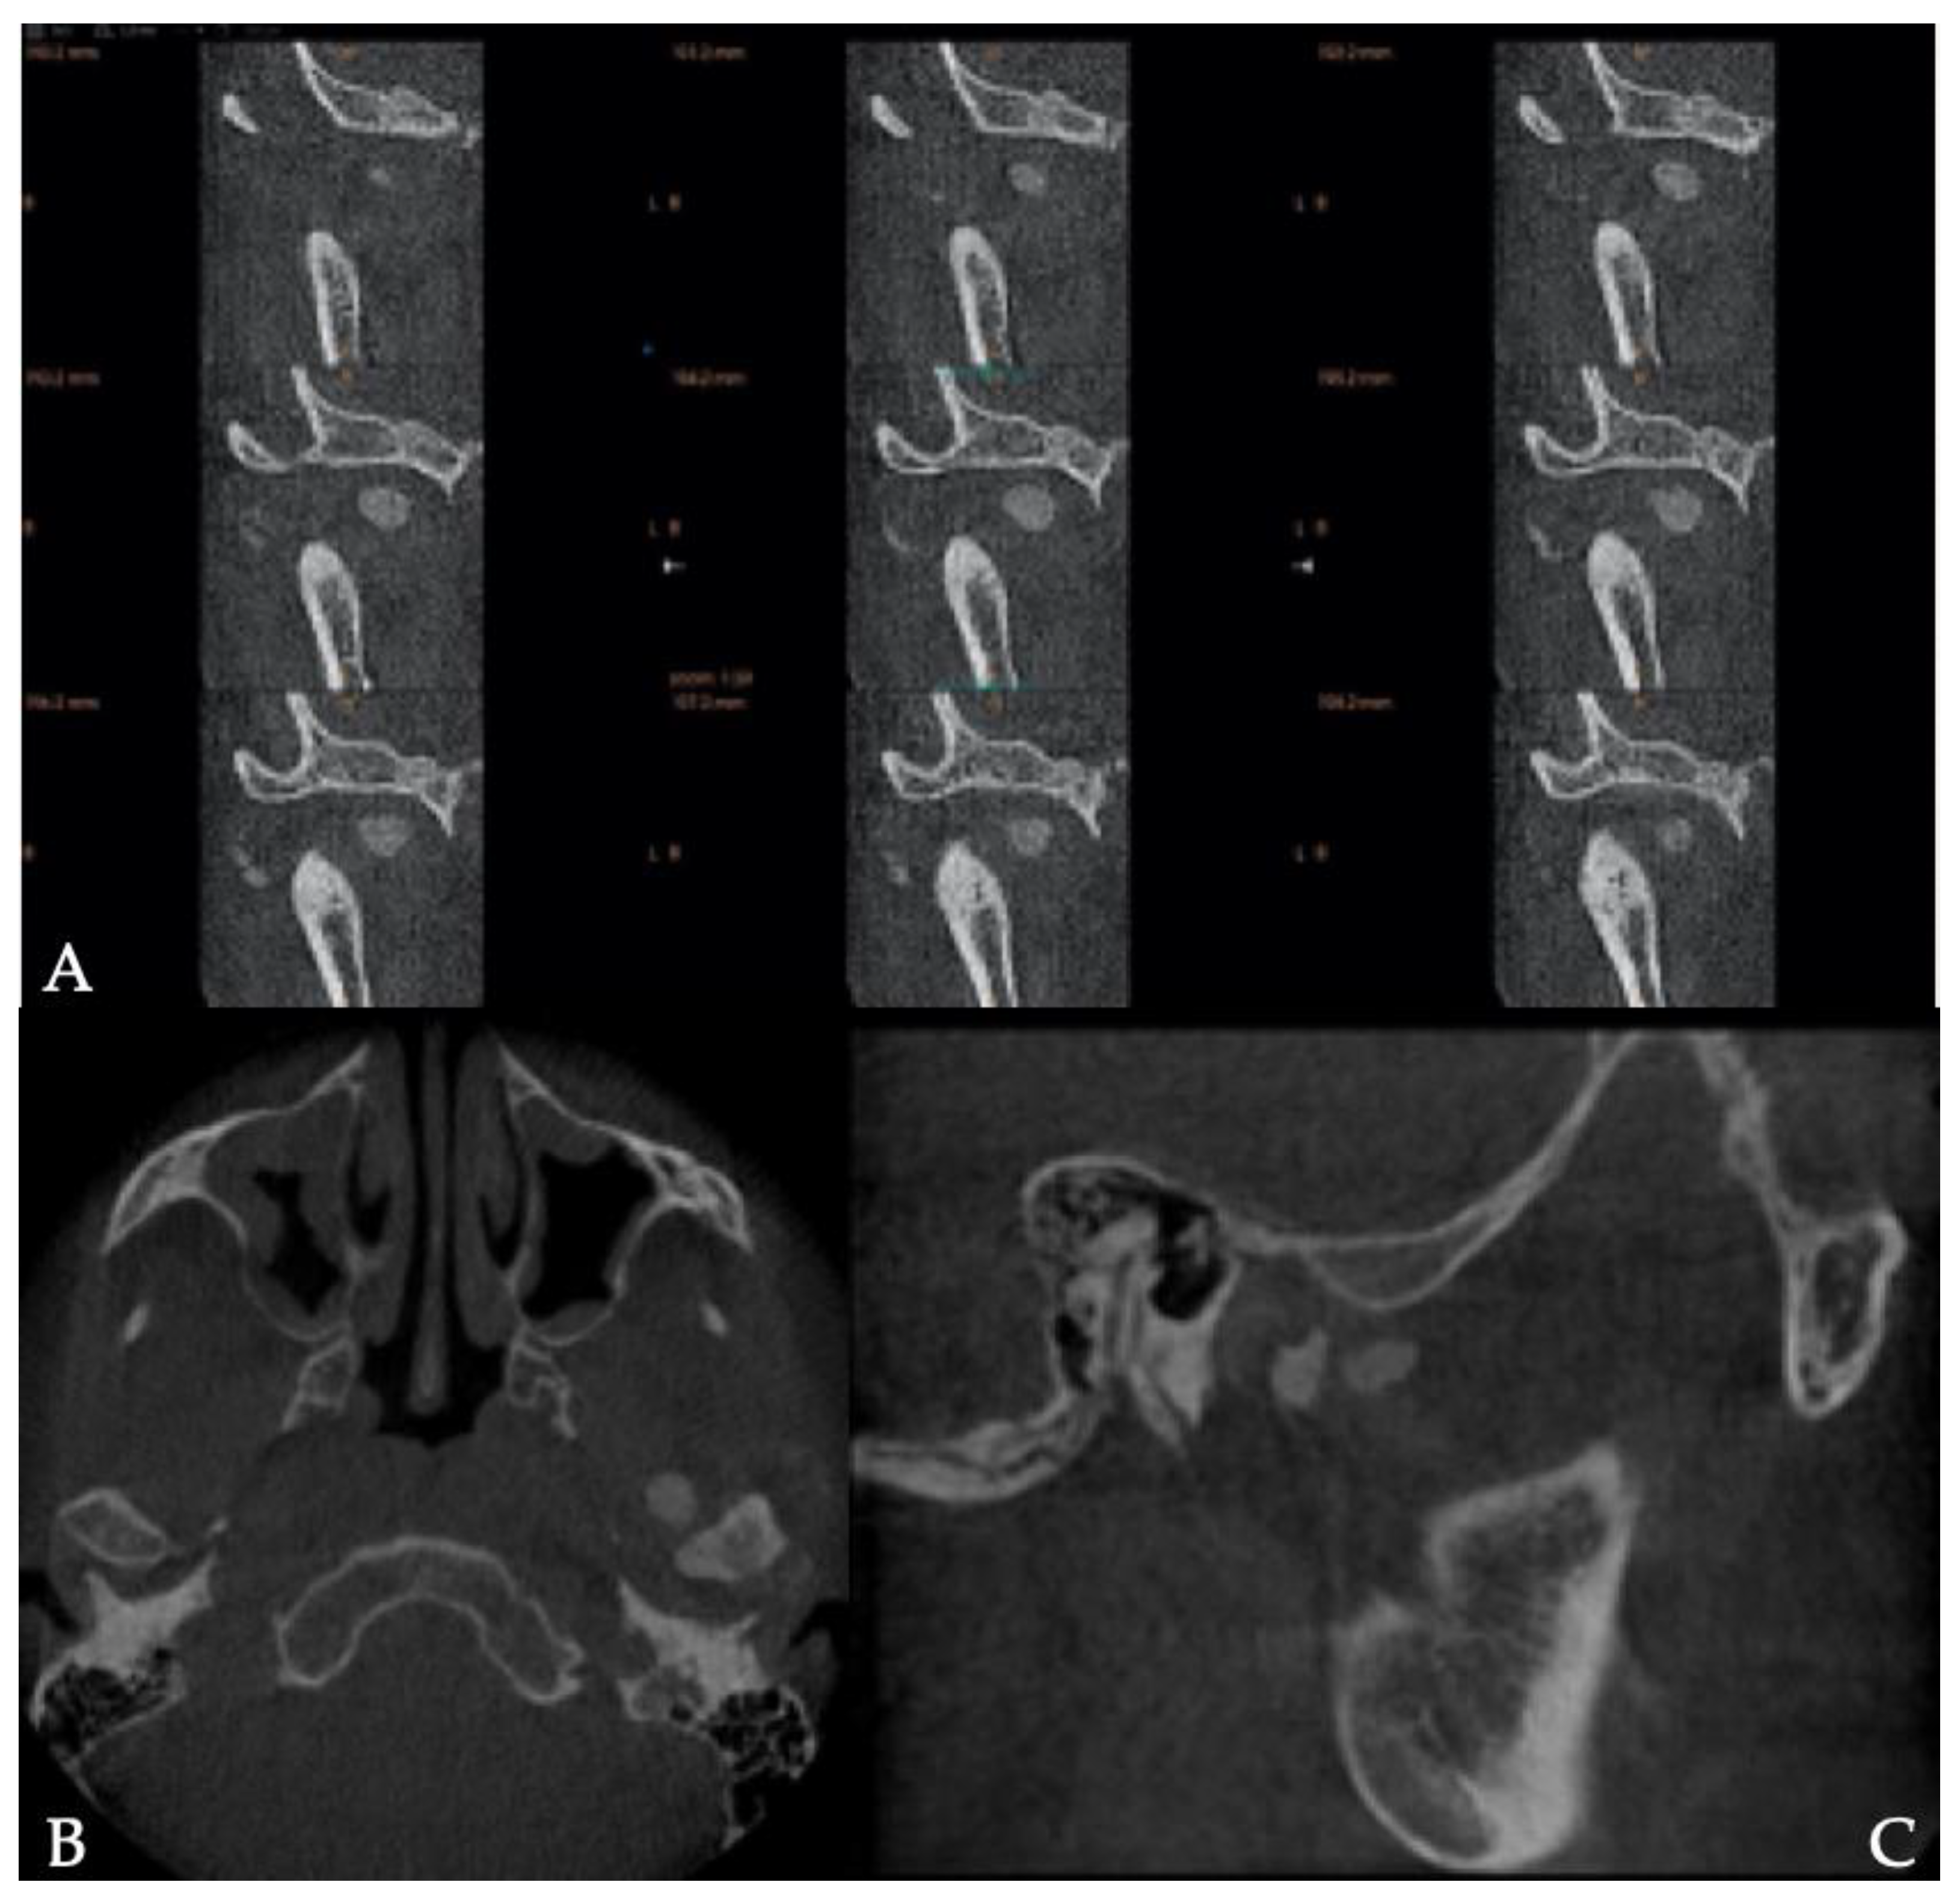

2. Case Presentation